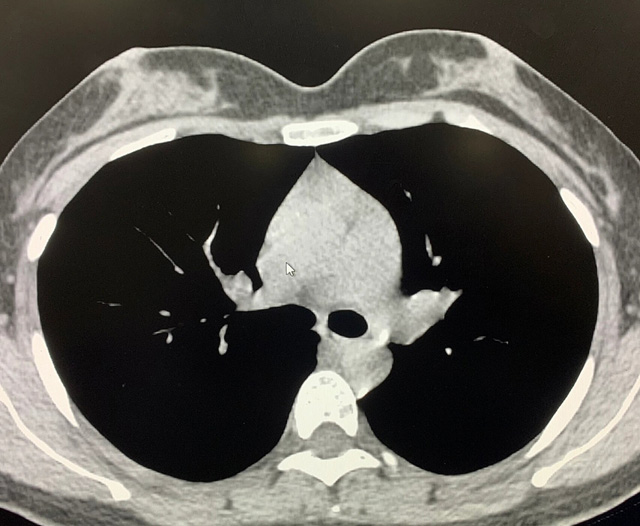

能譜純化技術的核心是通過物理濾過(如錫濾片)或軟件算法,選擇性濾除低能X射線光子,保留高能光子。在胸部低劑量CT掃描中顯著提升了圖像質(zhì)量與輻射劑量的平衡。

優(yōu)勢輻射劑量顯著降低相較于常規(guī)CT,輻射劑量減少約70%-90%,尤其適合需多次隨訪的高危人群(如肺癌篩查),降低輻射相關癌癥風險早期肺癌篩查效果明確可清晰檢測毫米級肺結(jié)節(jié),顯著提高早期肺癌檢出率,降低死亡率。檢查快捷且普及性高單次掃描僅需數(shù)秒,無需對比劑,設備廣泛配置于基層醫(yī)院,便于大規(guī)模篩查。長期成本效益顯著雖單次費用與常規(guī)CT相近,但早期干預可大幅降低晚期治療費用及社會醫(yī)療負擔。技術優(yōu)化提升圖像質(zhì)量迭代重建算法(如ASIR、MBIR)在降低劑量同時減少噪聲,平衡影像質(zhì)量與安全性。